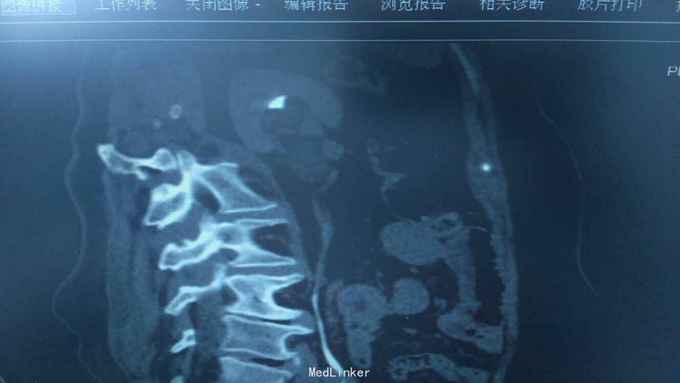

68岁,女性。 主诉:左侧腰痛1年,加重1个月。 病史:1年前无明显诱因出现左侧腰痛,无恶心呕吐,无肉眼血尿。1个月前加重,于外院查泌尿系彩超显示:左肾积液,输尿管显示不清。

诊断:双肾盂旁囊肿 治疗:因患者肾盂未明显受压,疼痛症状不明显,等待观察,暂未予处理。

双侧同时出现的病例并不多见,临床只能通过泌尿系统CTU或增强CT加以鉴别,彩超无法区分肾盂积水及盂旁囊肿。